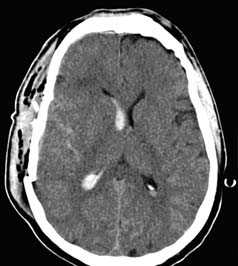

- выявить наличие пневмоцефалии.

КТ с внутривенным контрастированием (КТ-ангиография) по неотложным показаниям, как правило, не выполняется. Показанием к такому исследованию является обнаружение на нативных томограммых внутримозговых гематом, локализующихся в местах возможного разрыва аневнизмы.

Визуализация минимальных количеств излившейся свежей крови, уверенная дифференциация ее от других внеклеточных жидкостей, слежение за динамикой отека и набухания головного мозга, некроза и восстановления его структур с одновременным распознаванием переломов костей черепа, особенно его основания, составляют преимущества КТ перед магнитно-резонансной томографией.